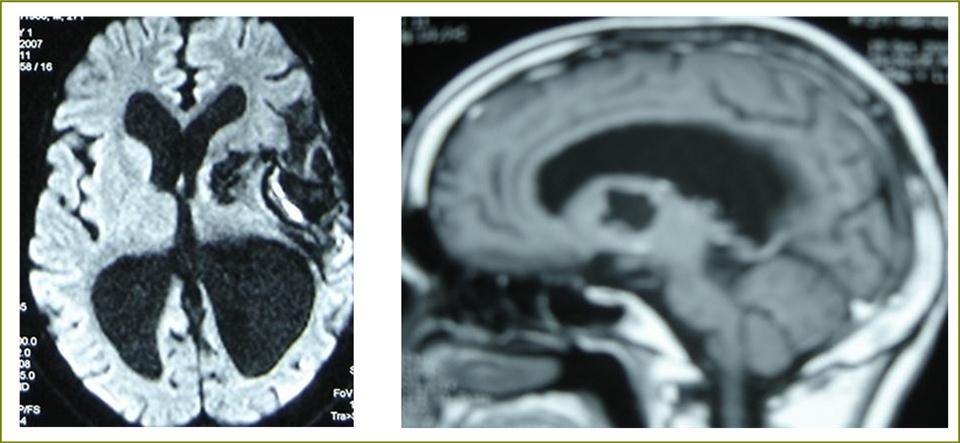

A 27 years-old male patient was admitted with 1 month history of headache, fever, short term memory lack, aphasia, right hemiparesis and seizures. He had liver hydatid cysts excised 8 years before and was treated with adjuvant medication (albendazole). The neurological examination revealed right central third cranial nerve palsy and hemi paresis, with Babinski sign positive, aphasia and papilledema on ocular fundus. The Glasgow Coma Scale was evaluated to 10/15 (E:3; V:1; M:6). A brain CT scan showed a large left temporoparietal intracerebral multiple and calcified hydatid cysts, important mass effect with midline shift about 7 mm following by an obstructive hydrocephalus (Figure 1). Other cysts were found in thalamic region (Figure 2). The Thoraco-abdominal CT scan showed multiple intra peritoneal hydatid cysts (Figure 3). A left temporo parietal craniotomy was performed in emergency. After corticectomy, using Arana-Iniguez technique, the appearance of the capsule suggested infected hydatid cysts with a purulent material which was aspirated. Numerous hydatid cysts were lifted away and several daughter vesicles were carefully removed without rupture (Figure 4). Macroscopically, the abscess wall appeared to be thick, calcified and tightly attached to lateral ventricular, so it could not be removed. The deep cyst overlying the third ventricle was left.in place. Microscopic examination demonstrated live scoleces, protoscoleces and multiple hooks. These findings are consistent with hydatid cyst (granulosis ecchinococcus) (Figure 5). Bacteriology examination found several white blood cells in the pus (neutrophilia) and infection by streptococcus pneumonia. This was consistent with infection. After surgery, the patient had medication (albendazole, specific antibiotherapy and phenobarbital). The inflammation assessment in the blood showed leukocytosis, a high C-reactive protein rate and increased erythrocyte sedimentation rate. Post operative CT scan was performed and showed the residual calcified capsule and decreased ventricular size (Figure 6). Clinical improvement was achieved after treatment. One month after the initial diagnosis, CT scan of the brain showed no recurrence and a physical examination revealed a neurologically intact, fully functional patient and eyes fundus normal. He was discharged and went to abdominal surgery two months later with complete intra abdominal cysts removal. Albendazole treatment was continuing for six months and radiological exploration was performed by brain MRI with spectroscopy at three and six month later. This showed that infection had resolved and the deep cyst overlying the third ventricle is less spherical (Figure 7, Figure 8). Four years later, the outcome was good.

Figure 8.sagittal T1 C+ MRI and axial spectroscopy showing the residual capsule and deep cyst which is less spherical.